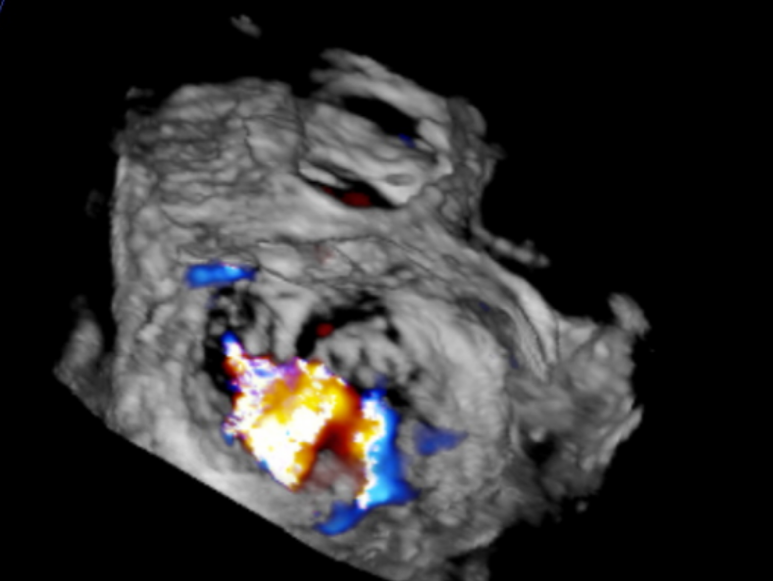

手术过程:手术采用经右侧股静脉入路,在TEE和DSA引导下完成房间隔穿刺,位置偏后偏上,穿刺高度为3.9厘米。置入瓣膜夹系统后,在左房调整瓣膜夹的轴向(orientation)和前进轨迹(trajectory),后进入左室进行瓣叶抓捕。由于两个瓣叶无法对合,后瓣叶较短,在尝试同时抓捕几次后,决定使用单独抓捕功能。先抓捕前瓣叶,再抓捕后瓣叶,确认瓣叶插入长度足够,缓慢关闭瓣膜夹。即刻返流程度降至轻度,跨瓣平均压差为2mmHg,最终成功释放瓣膜夹。采用“8”字缝合法关闭股静脉入路。术后肺静脉逆流和左房压都明显好转,预示着良好的预后。手术共耗时2小时,术后患者无明显不适,安返CCU继续观察。

术后TEE(≤1+)